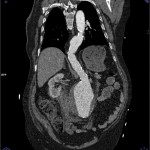

Para valorar la afectación en longitud la mejor prueba para hacerlo es la reconstrucción (MRP) , en planos sagital y coronal. Con las imágenes obtenidas en el TAC se hace una reconstrucción de todas obteniendo una imagen en un plano sagital y coronal. Con esta vista podemos ver la longitud y el diámetro exacto de la rotura del aneurisma y de de las zonas afectadas.

En la reconstrucción (MRP) en planos sagital y coronal se obtienen las siguientes imágenes: